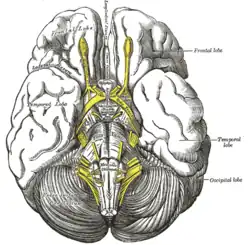

Tuber cinereum hamartoma is a benign tumor in which a disorganized collection of neurons and glia accumulate at the tuber cinereum of the hypothalamus on the floor of the third ventricle. It is a congenital malformation, included on the spectrum of gray matter heterotopias. Formation occurs during embryogenesis, typically between days 33 and 41 of gestation. Size of the tumor varies from one to three centimeters in diameter, with the mean being closer to the low end of this range. It is estimated to occur at a frequency of one in one million individuals.[1]

The classic presentation is gelastic or laughing epilepsy, a disorder characterized by spells of involuntary laughter with interval irritability and depressed mood. The tumor can be associated with other seizure types as well as precocious puberty and behavioral disorders. Gelastic epilepsy has been more classically associated with sessile lesions and precocious puberty reported with pedunculated morphology. More recent epidemiologic studies have found these associations to be less consistent, with gelastic epilepsy predominant in the majority of patients regardless of morphology.

Hypothalamic hamartomas are found in 33% of patients with true precocious puberty.[2] The etiology of this relationship is unclear, but it is suspected in some cases to be due to a nonphysiological secretion of GnRH.[3][4] A case of hamartoma has also been reported to secrete CRH, causing excessive ACTH production.[5]

Seizures often begin when patients are young, although studies have shown adult onset as well. Many causes of the epilepsy have been theorized, with EEG often finding the hamartoma itself as the source of electrical activity, or epileptogenic focus. With chronic seizures, cognitive decline can develop, which can manifest as poor school performance, decreased nervous stimulus IQ, or limited socialization. Other symptoms of this tumor type include visual disturbances, such as the appearance of motion from a stationary object, or inappropriate color perception of the entire visual field.[6]